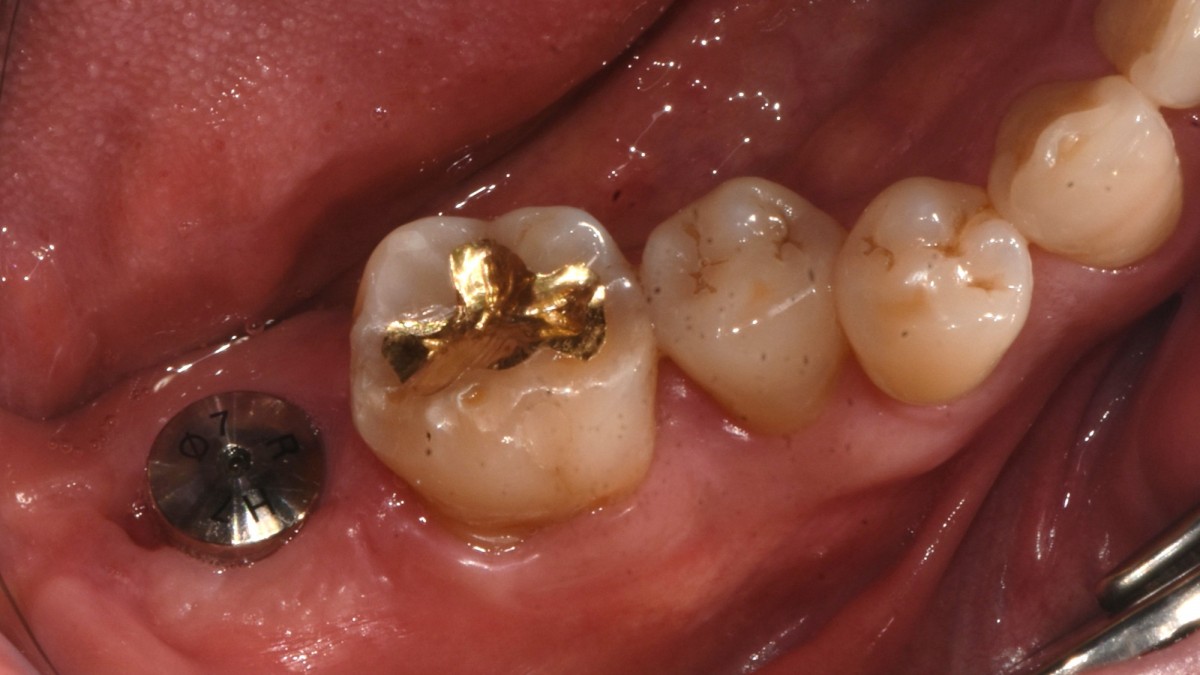

Single implant (staged) Arum NB1, f/u

▲torque value after insertion

▲Arum Dentistry NB1 5*10